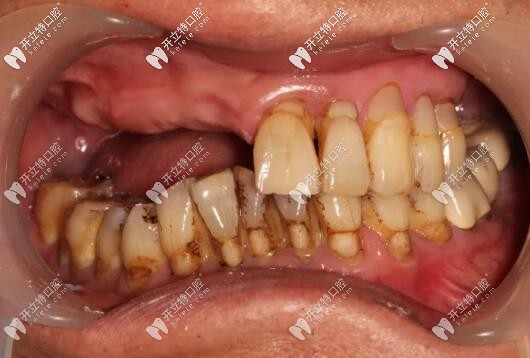

目前已完成ALL-ON-4即刻負(fù)重,通過手術(shù)情況來(lái)看,效果確實(shí)比較好,作為一位地道老陜?nèi)?,惠先生的感激之情溢于言表?/p>

西安美奧口腔即刻種植牙案例

西安美奧口腔半口種植牙案例

修復(fù)后